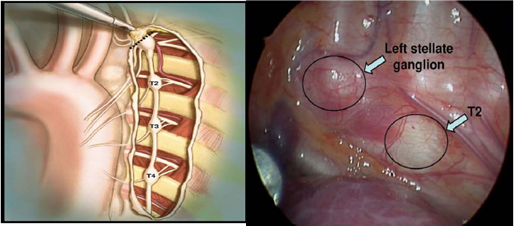

Cắt đốt thần kinh giao cảm ngực trái được chỉ định cho bệnh nhân. (Hình 5 và 6)

Hình 5. Thủ thuật nội soi lồng ngực với 3 trocars bên ngực trái (hình trái) tháng 12/2015. Mẫu bệnh phẩm sau bóc tách và đốt (hình phải).

Hình 6. Hình ảnh minh họa giải phẫu học các hạch giao cảm ngực trái (Hình trái) và hình ảnh nội soi trong khi phẫu thuât (Hình phải).